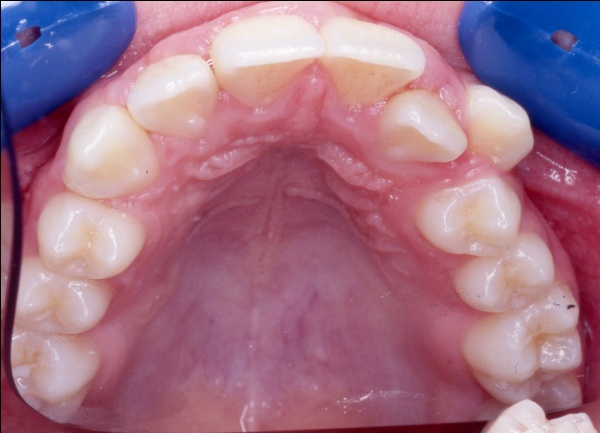

Ce cas illustre parfaitement que l’orthodontie ne peut pas se résumer à un simple alignement des dents. Ici, l’exclusion de la canine supérieure gauche (23) pouvait faire croire à un manque de place dû à un excès de volume dentaire. En réalité, un diagnostic précis a révélé deux causes : une endomaxillie (palais trop étroit) et une avancée anormale de l’hémiarcade gauche, qui empiétait sur l’espace de la canine. Le traitement a consisté à élargir le maxillaire par disjonction, puis à réaligner les dents sans extraction, en restaurant l’harmonie occlusale.

1 - Arcades avant/après

Le traitement a été conservateur, sans extraction, grâce à une thérapeutique de gain d’espace adaptée. L’arcade a retrouvé sa largeur, son équilibre et son esthétique, par la restitution d’une architecture osseuse et dentaire cohérente. L’occlusion est désormais fonctionnelle, stable et conforme aux rapports naturels entre les deux arcades.